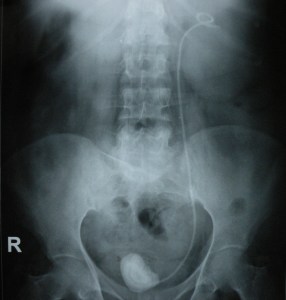

12.89.15

A stone grown on a forgotten DJ ureteric stent. The stent had been there for more than 10 years. Both the stent and stone were removed via a cystostomy.